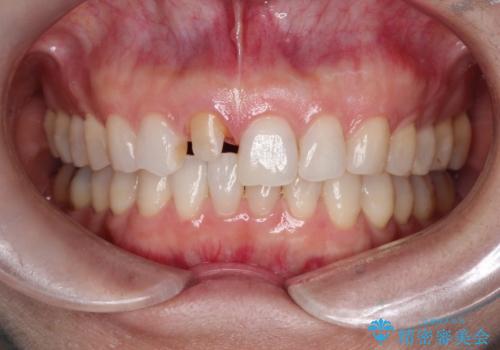

- 「他院で治療した前歯の被せものが一か月の間に2回外れたのでやり変えたい」を主訴に来院されました。

10年前に根管治療を他院で行っており、根尖性歯周炎の予防のため根管治療から行いました。被せものはオールセラミッククラウンで治療を行いました。

ホワイトニングもご希望されたのでホームホワイトニングも行いました。

10年前にラバーダムシート無しに根管治療を行っており、現在、症状は出ていませんが、根尖性歯周炎の予防のため根管治療から行いました。ホームホワイトニングを2週間行って頂き、その後、オールセラミッククラウンで治療を行っています。